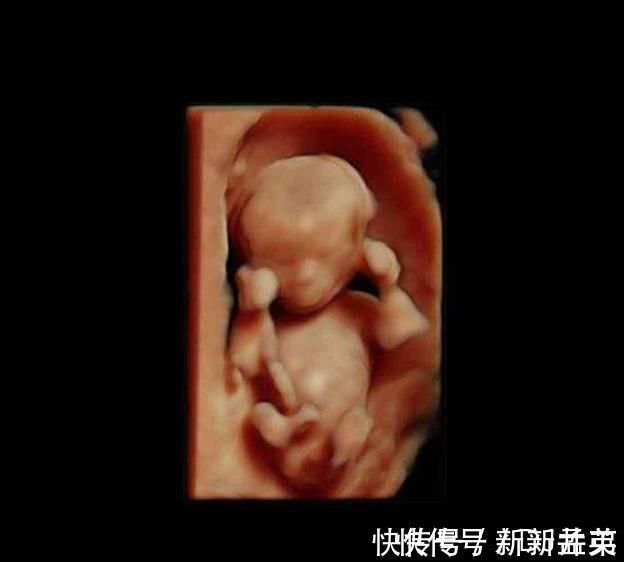

进入第10周,胎儿的发育更细致了,比如眼睛和眼睑已经融合,眼睛清晰可见,手臂和胳膊等都很清楚,此时的胎儿开始发阿玉生殖器官,不过肉眼是看不出来性别的。